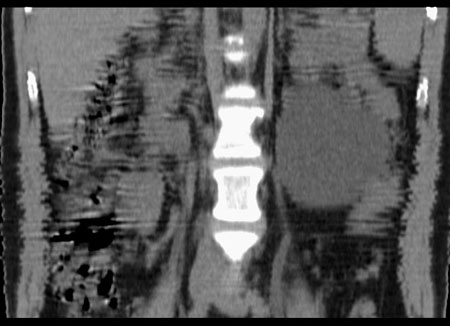

m29y平常体健,无明显不适。单位体检时发现左肾区病变。来我院作ct如下(病人不做增强):

左侧输尿管冠、矢状重建: